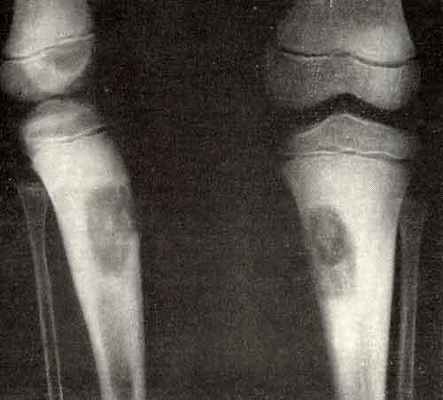

Фиброма костей характеризуется очаговой резорбцией (рассасыванием) кортикального слоя отдела трубчатой кости с замещением его на фиброзную. Образуется в бедренной, берцовой, плечевой и пяточной костях. Чаще всего встречается у детей и подростков. Во многих случаях приводит к патологическим переломам.

- неоссифицирующая фиброма – доброкачественный фиброзный дефект костной ткани;

- оссифицирующая фиброма – редкое фиброзно-костное доброкачественное новообразование у детей и лиц молодого возраста;

Неостеогенные опухоли образуются в бедренной кости и провоцируют разрушение трубчатых костей скелета. В запущенной стадии заболевание становится причиной патологического перелома кости. Редко (3–5% клинически диагностируемых случаев) новообразование уменьшается в размерах без хирургического вмешательства. Другие виды костных опухолей отличаются агрессивным ростом. Так, десмопластическая фиброма способна увеличиться в объеме вдвое за 2–3 недели.